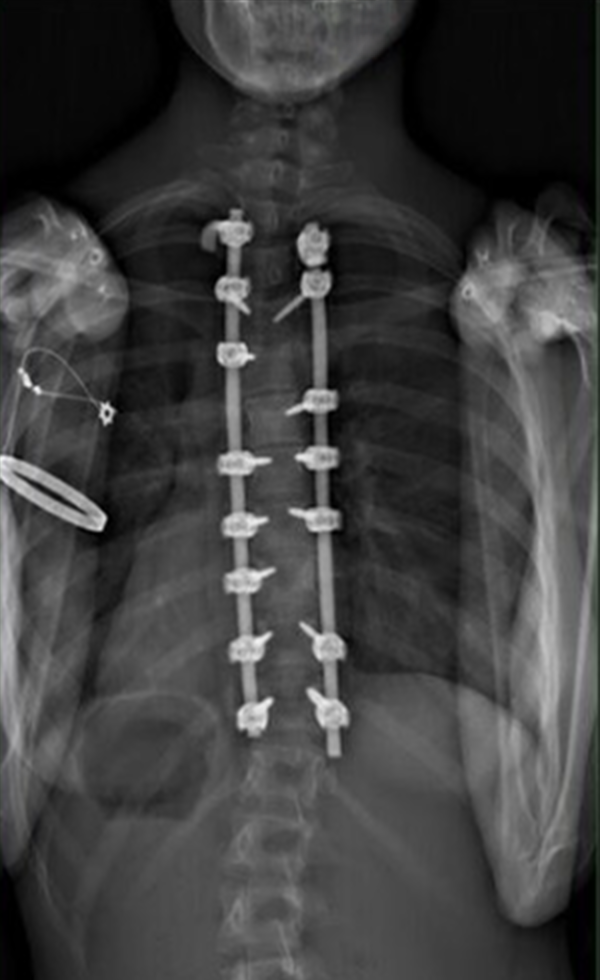

Gallery : Before - After